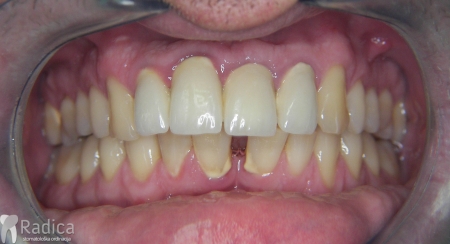

U sljedećem primjeru su se na mjesto donjih ekstrahiranih prvih molara stavili dentalni implantati prije ortodontske terapije (rad dr. Gorana Radice) i ujedino su služili za pojačenje sidrišta tijekom ortodontske terapije. Nakon ortodontske terapije estetski su se preoblikovali sjekutići i napravile nove krunice (također rad dr. Gorana Radice).